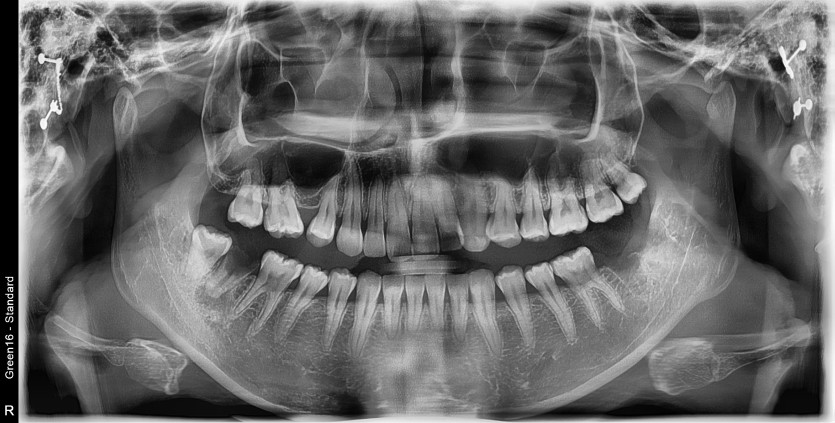

#38,48 (#37,47 포함) 사랑니 발치

구강 외과 전문의가 당일 발치했습니다.